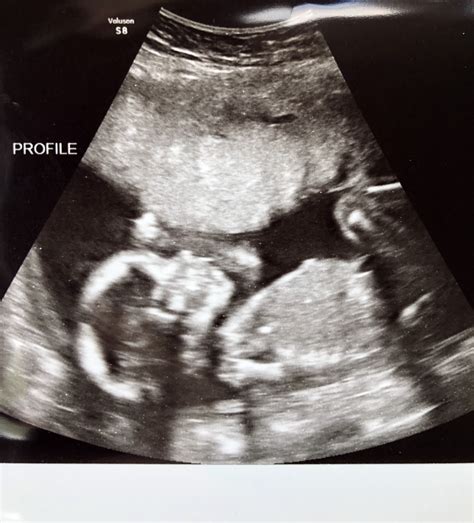

Ultrasound scan of a fetus

The 11 week ultrasound is typically performed either abdominally or transvaginally, depending on factors such as your body type and the position of the uterus. For most women at 11 weeks, an abdominal ultrasound is sufficient, where a transducer is moved over the belly with gel. However, if a clearer image is needed, a transvaginal approach may be used. The entire process is generally painless, though it can feel a bit cold due to the conductive gel.

During the appointment, the sonographer or doctor will focus on several key aspects to ensure the pregnancy is progressing as expected. They are not just looking for a heartbeat; they are assessing anatomical development and ensuring the pregnancy is located safely within the uterus. It is a moment of wonder for many, as you can often see the baby moving, though you may not feel those movements yet.

By the 11th week, your baby is roughly the size of a lime or a Brussels sprout, measuring about 1.5 to 2 inches long. Despite their small size, they are incredibly active. During the 11 week ultrasound, you might be surprised to see your baby performing various movements, such as curling their toes, stretching, or even hiccuping.

• Movement: You will likely see the baby wriggling and stretching, which is a sign of healthy neuromuscular development.